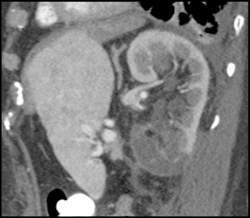

Renal Angiomyolipoma (AML)